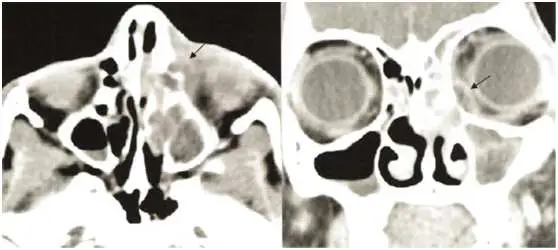

本題核心在於 CT 影像上判斷膿液聚積是在何處。

影像分析:

CT 影像(橫斷面與冠狀面)顯示在鼻側眼窩骨板(lamina papyracea)與內眼窩骨膜(periorbita)之間,出現一片邊緣清楚的低密度液體集合(黑色箭頭所指)。膿液將骨膜輕微向外推擠,但骨膜並未被破壞或穿透;眼球略有前突,但眶內脂肪組織仍基本正常。這種位於骨膜與骨壁之間的局限性流體囊腔,符合典型的 subperiosteal abscess 影像特徵(ijponline.biomedcentral.com)。